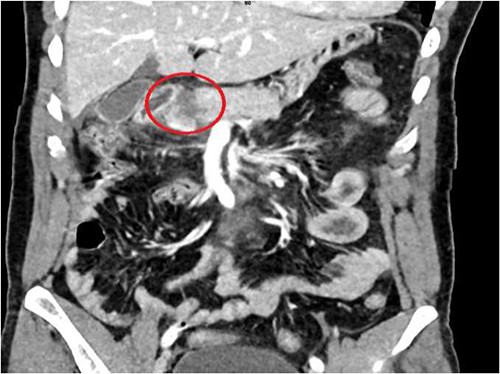

A 36-year-old male manual laborer was assaulted by his roommates (kicked in the abdomen multiple times) and was intoxicated with alcohol. He was writhing in pain, hemodynamically stable with a guarding abdomen. Initial laboratory results showed high serum amylase level 485 U/L, high serum lipase 1200 U/L and elevated liver enzymes. A computed tomography (CT) scan revealed an enlarged bulky head of the pancreas with complete transection of the pancreatic neck (Figs 1–2). In addition, he had a small contusion of the liver and free fluid in the abdomen.

CT abdomen—coronal section, showing transection of the pancreas (circle).